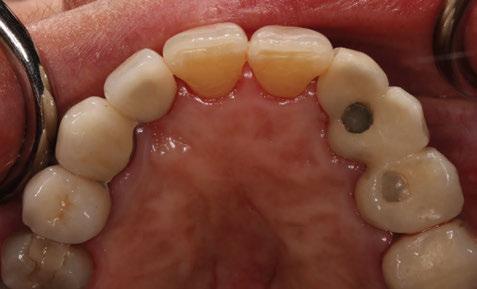

-Registros fotográficos intra y extraorales (Figura 1 a-c).

-Estudio radiográfico inicial (ortopantomografía y radiografías periapicales) (Figura 2).

-Escáner intraoral mediante iTero Element™2 con el fin de obtener modelos digitales (archivos STL) (Figura 3).

A partir del estudio radiológico y de las imágenes fotográficas podemos observar edentulismo de 17, 15, 14, 12,

Figura 1a. Foto intraoral frontal inicial.

Figura 1b. Foto intraoral lateral izquierda inicial.

Figura 1c. Foto intraoral lateral derecha inicial.

Figura 2. Ortopantomografía inicial.

25, 26, 28, 37, 38, 47 y 48. Presentaba corona desajustada en 13 con extensión en 12, implantes en 35-36, 45-46, con coronas ferulizadas en 35-36, 45-46, y dientes anteriores superiores con enfermedad periodontal Grado IV.